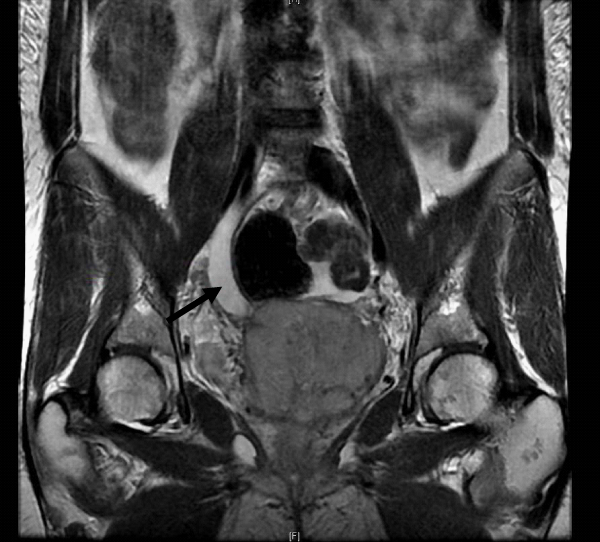

MRI revealed a large pelvic mass extending from the cervix that was associated with severe right hydroureter, anterior displacement of the bladder, and bladder invasion at the level of the trigone (Figure 1). On cystoscopy, the bladder base, lateral walls, anterior wall and dome were free of lesions; however gross intraluminal tumor was protruding from the right ureteral orifice (Figure 2). A biopsy of the tumor was taken and the patient underwent right PCN placement. Pathologic analysis from the biopsy revealed adenocarcinoma consistent with an endocervical origin. Based on the pathologic findings, the patient’s disease was classified as stage IVA and she was started on platinum-based chemotherapy and pelvic radiation.

Figure 2 Right ureteral orifice with protrusion of papillary tumor of endocervical origin. Surrounding bladder mucosa is unremarkable.